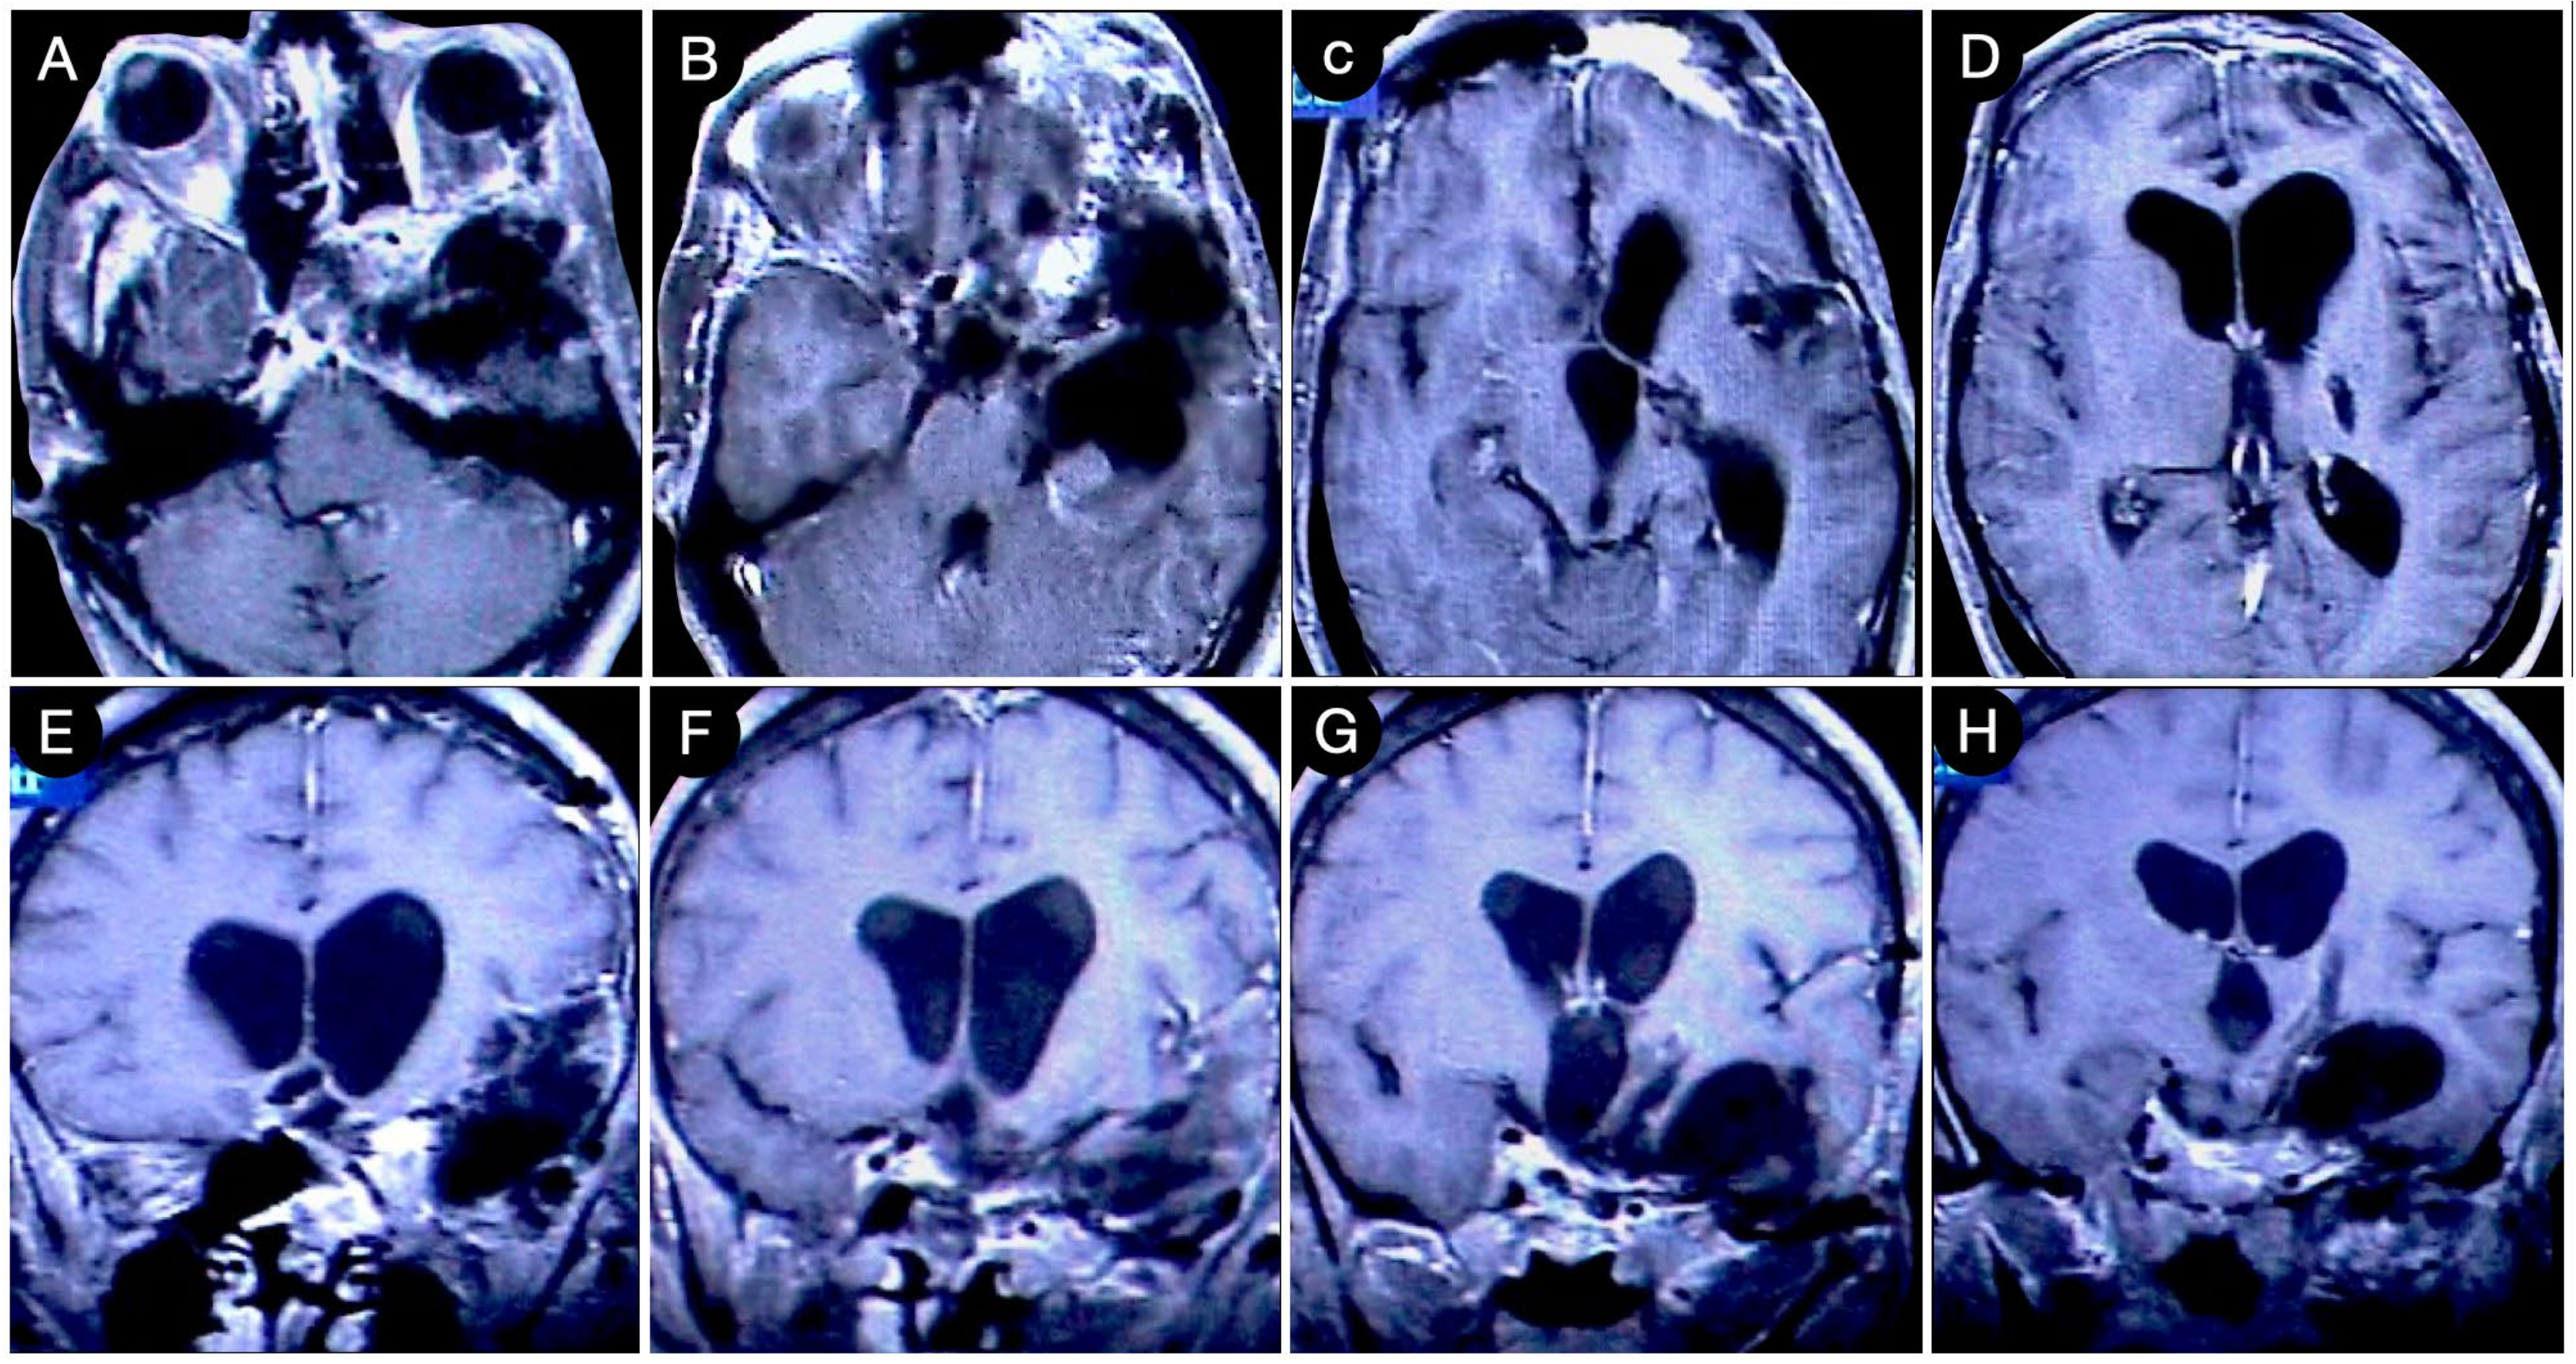

Case #8: Aggressive ACTH Tumor with Multiple Recurrences